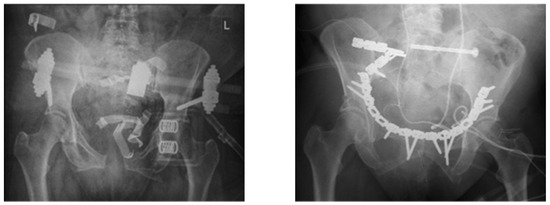

| Stabilization Method | anterior | 15× plate | 1× plate | 16× plate |

| 1× Fix ex | 4× Fix ex | 5× Fix ex | ||

| posterior | 7× screws | 3× screws | 10× screws | |

| 2× plate | 2× plate | 4× plate | ||

| 3× TIFI | 2× TIFI | 5× TIFI | ||

| 2× lumbo-pelvic | 1× lumbo-pelvic | 3× lumbo-pelvic | ||